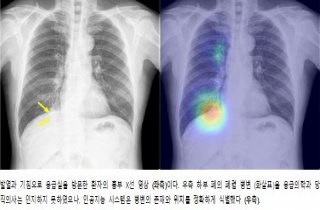

¼­¿ï´ëº´¿ø ´çÁ÷ÀÇ»ç vs ÀΰøÁö´É 'ÈäºÎ¿µ»ó ÆÇµ¶' °á°ú

±¹³» ¿¬±¸ÁøÀÌ ½ÇÁ¦ ÀÇ·áÇöÀå¿¡¼­ ÀΰøÁö´É(AI) Áø´Ü½Ã½ºÅÛ È°¿ë °¡´É¼ºÀ» ÀÔÁõÇß´Ù. ¼­¿ï´ëÇб³º´¿ø ¿µ»óÀÇÇаú ¹Úâ¹Î, Ȳ.2019-11-06 11:13:47